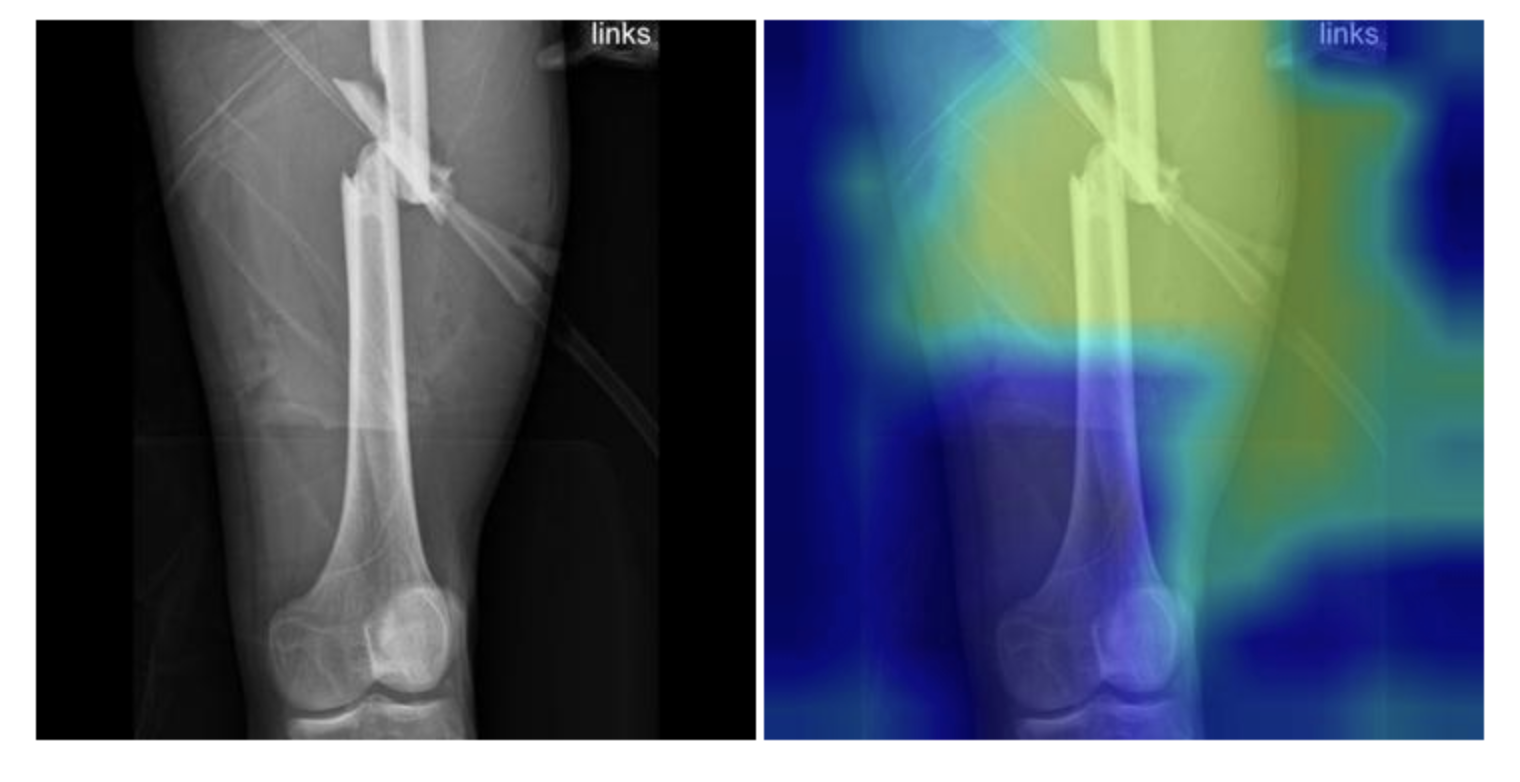

Refer to caption

Figure 1: Example of the fracture detection on the leg bone